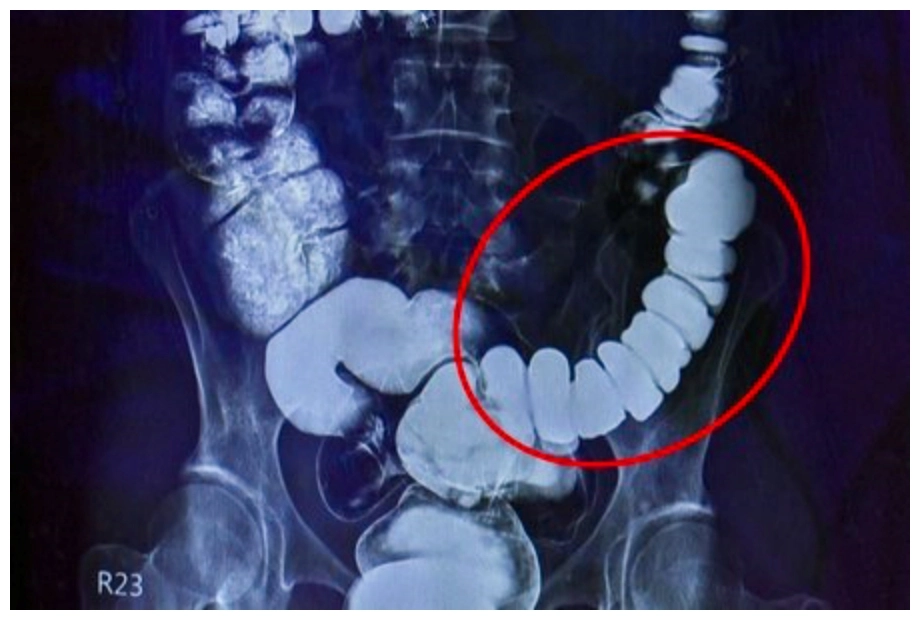

大腸可說是人體的第二個大腦,腸子緊繃,表示情緒壓力反應在腸道上,易造成便祕。(圖片來源/《人醫心傳第232期》)

經過大腸攝影檢查,邱建銘發現江女士的腸子繃得非常緊,這是典型情緒影響腸道的病例,雖然臨床不算少,但邱建銘仍不免驚訝:「沒看過把自己腸子逼得這麼緊的。」